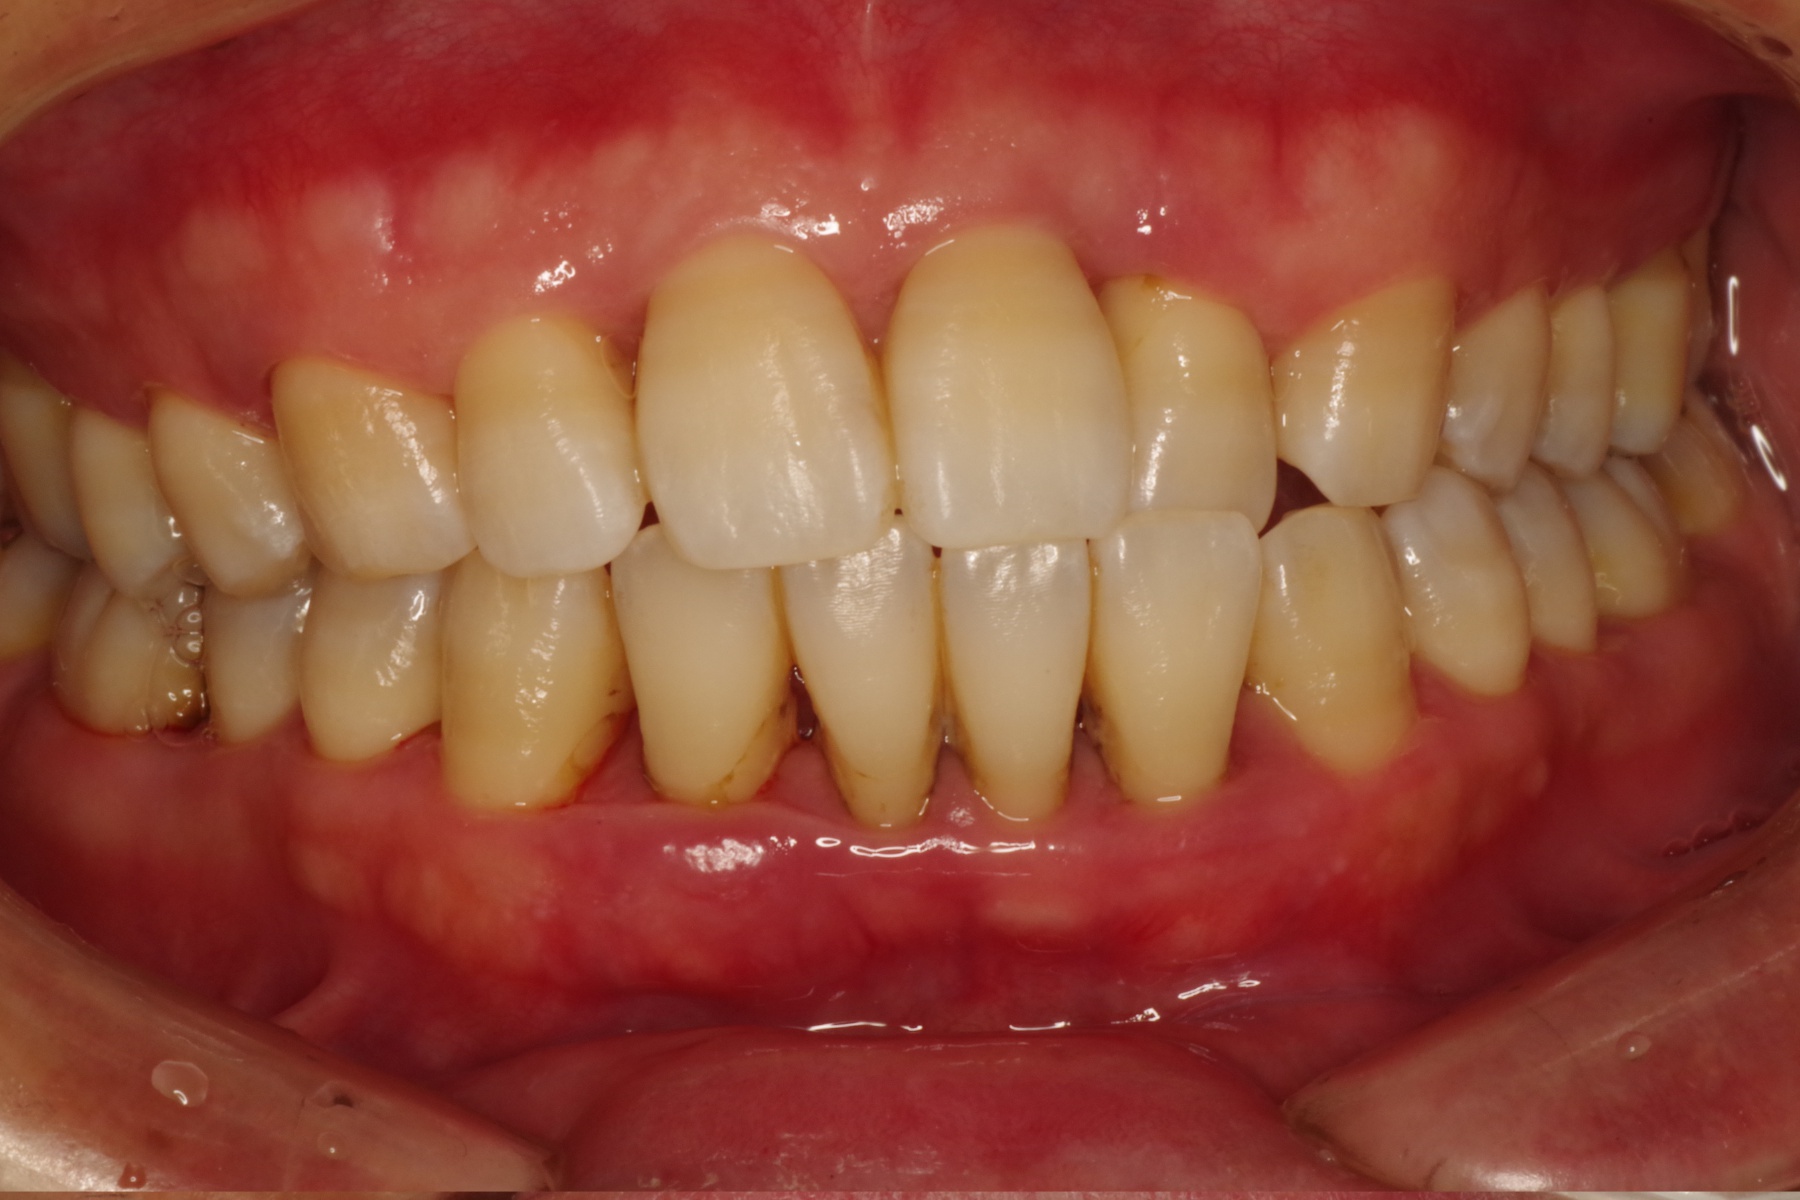

歯肉が赤く腫れる感じは・・。

歯周病が進むと顎の骨を溶かし、最悪の場合、歯が抜けてしまいます。

虫歯が家の壁が壊される事としたら、歯周病は家の土台が壊されるような病気です。

歯周病は虫歯より痛みが出るのが遅いため、早期発見が大切です。

当医院では歯茎の検査やお口全体のレントゲン写真を用い、歯周病の有無を確認いたします。

歯周病の程度により治療内容や診察回数が異なりますのでまずはご相談下さい。

もっと大切は歯周病にならない様普段のお口のケアが大切です。

定期的な健診をお薦めします。